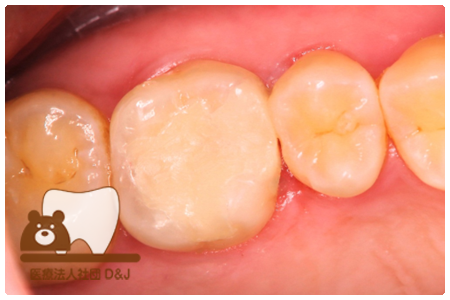

症例8フルジルコニアクラウン

治療前

治療中

治療後

29歳 女性

- 治療内容

- 銀歯からフルジルコニアクラウンへの修復

- 治療期間

- 根の治療含め3か月

- 費用

- 自費

フルジルコニアクラウン:77,000円(税込)

- その他の治療の費用は含まれておりません。

- リスク・副作用

- 強い衝撃が加わると欠けたり割れたりする可能性があります。また、噛み合わせの状態によっては脱離や周囲の歯への影響が出ることもあります。